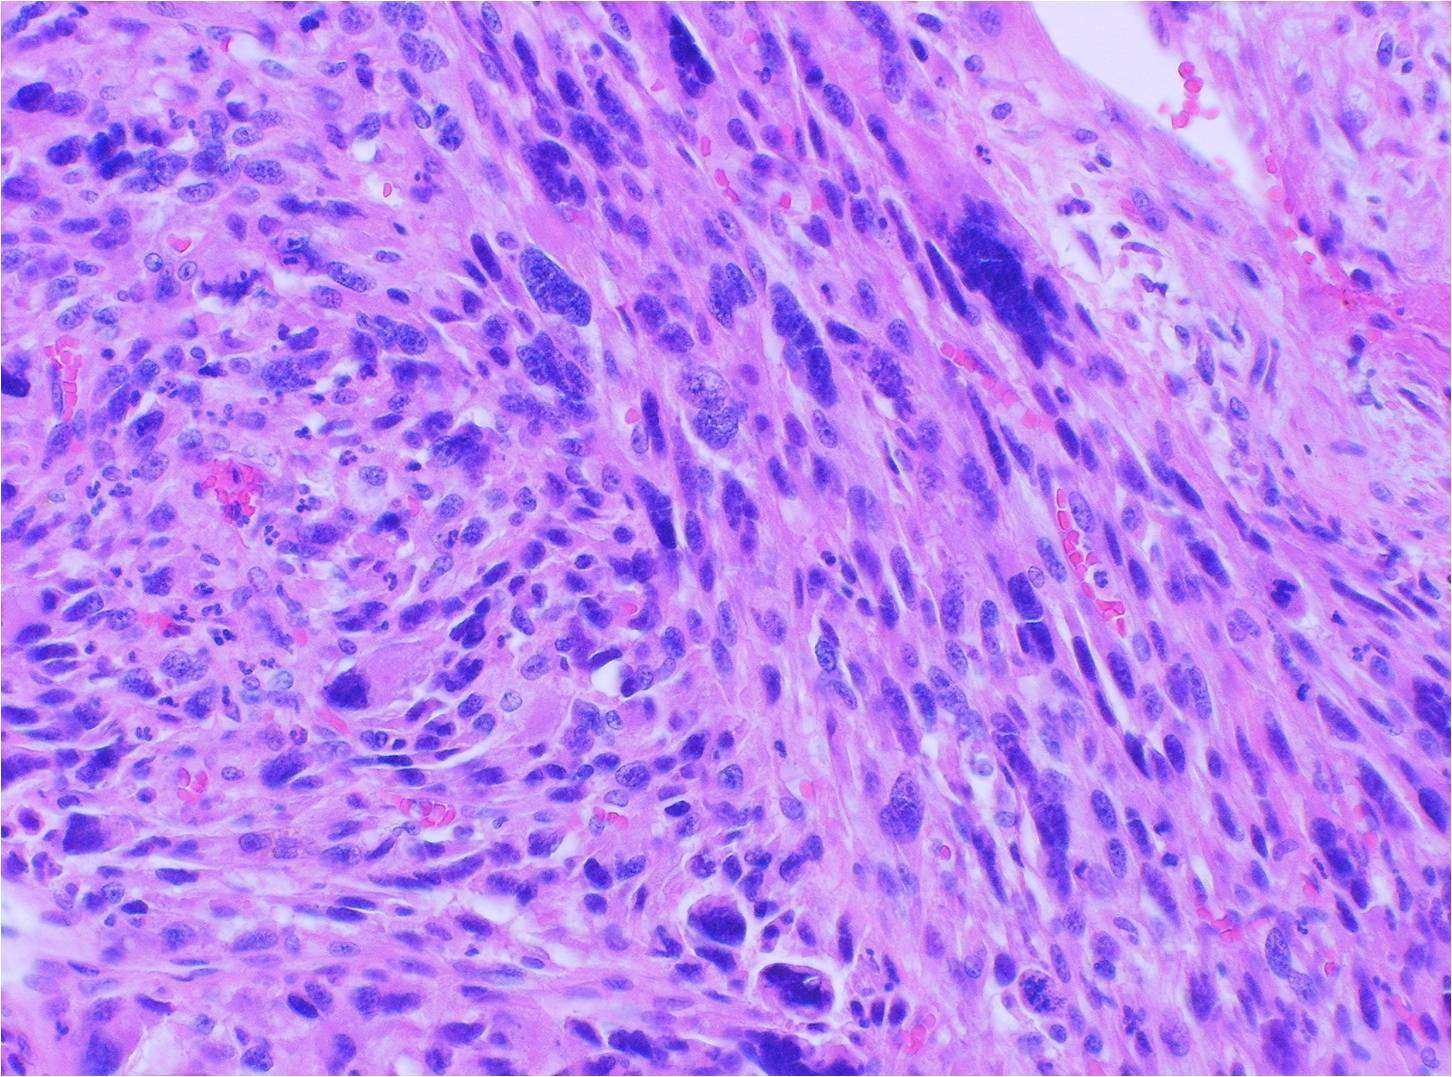

FileMalignant spindle cell neoplasm showing mitotic figures 40X.jpg Spindle Cell Neoplasm With Atypia Cutaneous spindle cell neoplasms are relatively common and present surgical pathologists with diagnostic challenges. Spindle cell neoplasms arising in the skin comprise a heterogeneous group of tumors with divergent lineages. Atypical spindle cell/pleomorphic lipomatous tumor (ascplt) is a rare and recently described adipocytic neoplasm that primarily. Atypical spindle cell/pleomorphic lipomatous tumor (ascplt) is a novel entity of benign adipocytic neoplasm. Spindle Cell Neoplasm With Atypia.